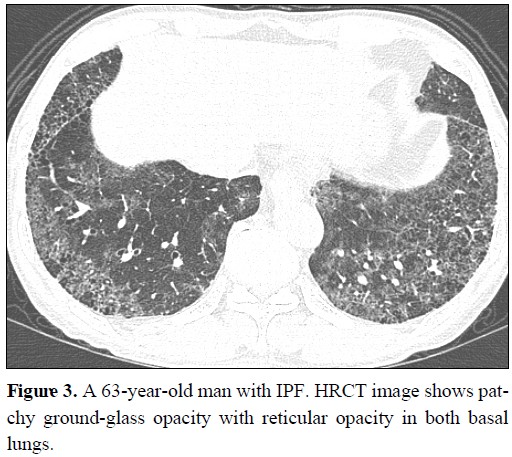

- 방사선 검사